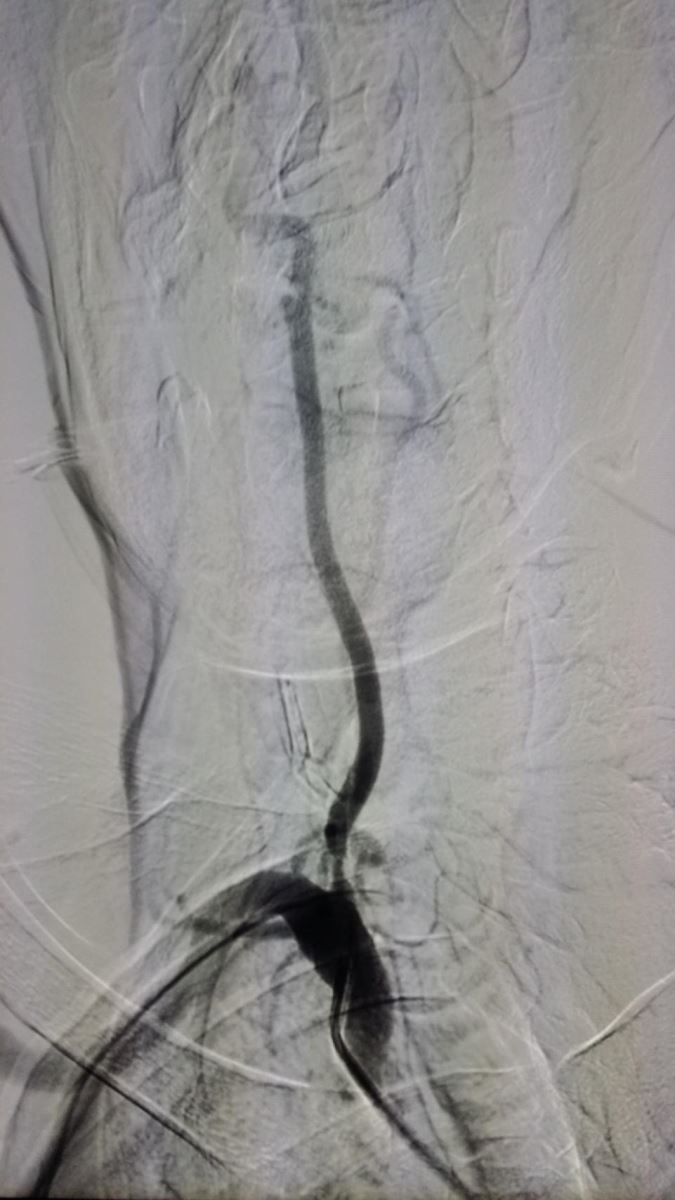

椎动脉支架手术示例(右侧椎动脉起始部):

术前 支架植入后